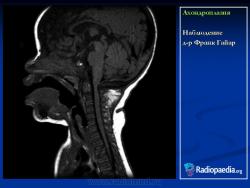

Наблюдение д-ра Франк Гайар

Ахондроплазия

Ахондроплази́я (диафизарная аплазия, болезнь Парро-Мари, врожденная хондродистрофия) — известное с древности наследственное заболевание человека, проявляющееся в нарушении процессов энхондрального окостенения (вероятно, в результате дефектов окислительного фосфорилирования) на фоне нормальных эпостального и периостального окостенений, что ведет к карликовости за счет недоразвития длинных костей; характеризуется наличием врождённых аномалий, в частности врождённого стеноза позвоночного канала. Наследуется по аутосомно-доминантному типу.